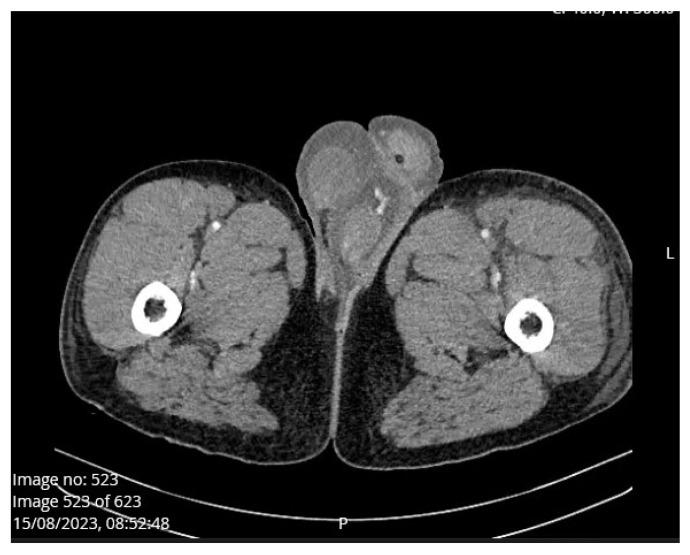

: Scrotal swelling or hydrocele is a rare complication of acute pancreatitis described in the literature. We present a case of penoscrotal swelling caused by the first attack of acute interstitial edematous alcohol-induced pancreatitis in a young male patient. : A 22-year-old man was admitted to the emergency unit due to diarrhea and vomiting since morning which was followed by severe abdominal pain. Urgent abdominal multislice CT scan showed steatosis, pancreatic swelling and acute peripancreatic fluid collection (interstitial edematous pancreatitis). Also, scan showed fluid between small bowel loops and along the anterior renal fascia, while there was minimal amount of fluid in the Douglas space. There was no sign of penoscrotal swelling. On the second day of admission, the patient developed left scrotal swelling and mild pain without erythema. On the fourth day, a control CT scan showed progression to moderately severe pancreatitis (CT severity index 4). Dilated scrotal veins of the pampiniform venous plexus with an increased caliber of the testicular veins were present on both sides, from the scrotum to the level of the inguinal canal. Penoscrotal swelling was significantly reduced on discharge. : Penoscrotal swelling is a rare complication or manifestation of acute inflammation of the pancreas. It is important to identify scrotal swelling caused by pancreatitis because in severe cases it can be related to possible infertility in the future.

一名 22 岁男性因腹泻和呕吐于当天上午入院,随后出现严重腹痛。紧急腹部多层 CT 扫描显示脂肪变性、胰腺肿胀和急性胰周液体积聚(间质性水肿性胰腺炎)。此外,扫描显示小肠环之间和前肾筋膜处有液体,而道格拉斯间隙内液体量较少。没有阴囊肿胀的迹象。入院第二天,患者出现左侧阴囊肿胀和轻度疼痛,但无红斑。入院第四天,对照 CT 扫描显示胰腺炎进展为中度重症(CT 严重指数 4)。双侧阴囊内精索蔓状静脉丛扩张,睾丸静脉增粗,从阴囊延伸至腹股沟管水平。出院时阴囊肿胀明显减轻。